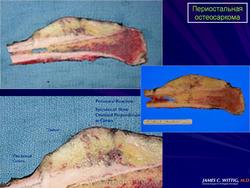

Макроскопически опухоль мягкая, дольчатого строения, имеет вид хрящевой ткани голубовато-серого цвета. Наружные края опухоли хорошо ограничены и обычно не отмечается инфильтрации в прилежащие ткани. Опухоль минимально инфильтрирует кортикальную пластинку и никогда не распространяется в костномозговую полость.

Макроскопическая картина при периостальной остеосаркоме складывается из фокусов дольчатой, преимущественно хрящевидной, белесоватой опухолевой ткани на поверхности кортикальной пластинки кости без внедрения в костномозговой канал.